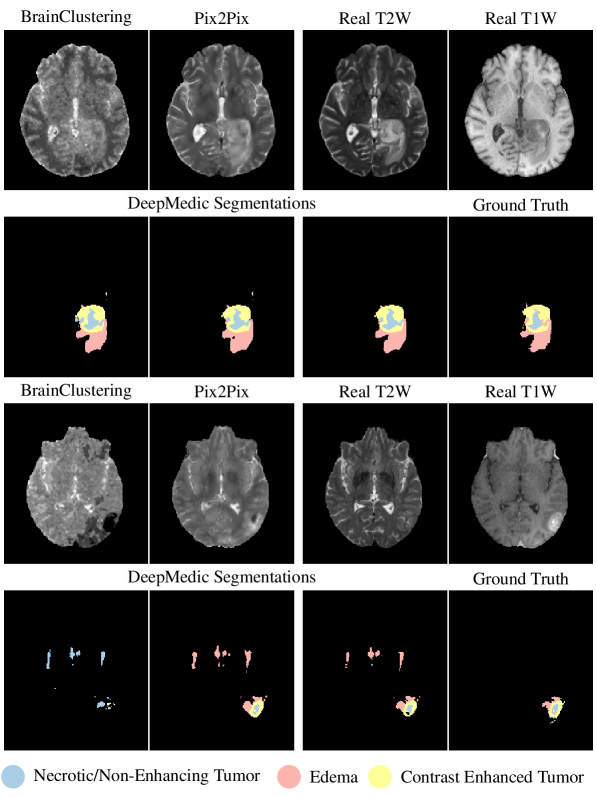

Figure 3 up to Figure 5 give a visual impression of the resulting synthesized images for the testOUR data set. In Figure 3, we present two synthesized images produced by BrainClustering and Pix2Pix for two patients. The second and fourth row show the segmentation achieved by using the respective image as T2W. The rightmost image in the “Real T1W” column shows the ground truth image and segmentation. Figure 4 and Figure 5 present the middle transversal slice for each MRI in testOUR with the segmentation superimposed on the scans.

Refer to caption

Figure 3: The segmentations in the second and in the fourth row have been created using the respective T2W and the three original T1W, T1CE, FLAIR. The rightmost image in the “Real T1W” column shows the real T1W image and the ground truth segmentation.